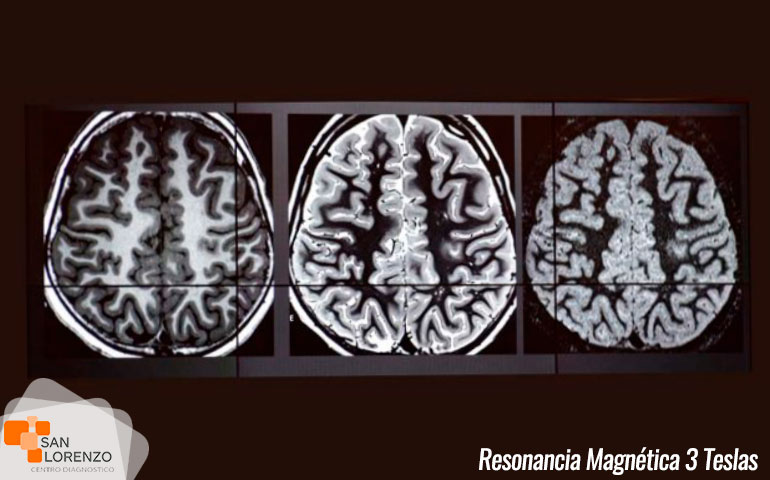

Centro de diagnóstico San Lorenzo, gracias a la mejora continua a nivel de tecnología en imágenes, cuenta actualmente con un resonador magnético General Electric de 3 teslas, uno de los únicos resonadores de estas características en la región de O’Higgins y zona centro sur, que permite el diagnóstico de diversas patologías como tumores, cáncer y otras enfermedades cada vez más comunes y complejas, permitiendo este estudio el acceso a todos los habitantes de Rancagua a Punta Arenas.

Algunas de las ventajas de la resonancia magnética 3 Teslas:

• Su tecnología hace posible adquirir en una secuencia, imágenes sintéticas con distintas ponderaciones de contraste.

• Apoyo diagnóstico en patologías de alta complejidad, especialmente a nivel osteoarticular, músculo esquelético y estudios cardíacos.

• Tecnología de vanguardia que permite hacer adquisiciones volumétricas y más planos en una sola secuencia.